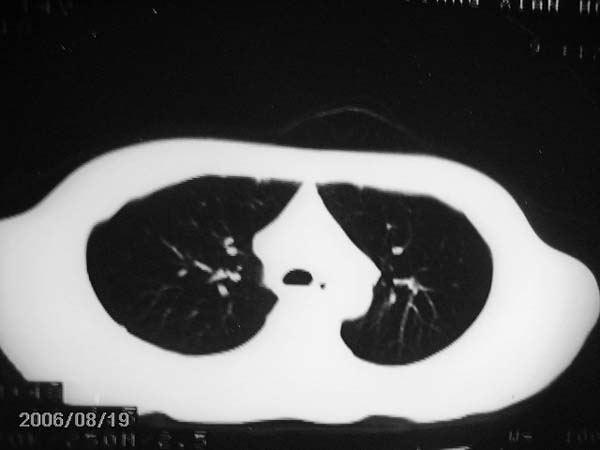

男,13岁,发烧半月,干咳无痰,正规使用抗生素半月,现在仍是午后低烧!!!未做痰检

结合临床考虑:右肺中叶结核可能性大.

右肺中叶结核可能性大

右肺结核,右肺中叶不张

右侧肺门淋巴结好象有增大,会不会是个原发综合症合并感染

右中肺呈大片状密度欠均匀影,内见含气支气管.

结合病史,考虑:右中肺大叶性肺炎(吸收期).

右肺中叶大片状密度增高影,内密度不均匀,右肺门处增大,应该是淋巴结肿大,结合临床首先考虑原发性肺结合可能性大,不排除合并感染可能,建议治疗后复查.